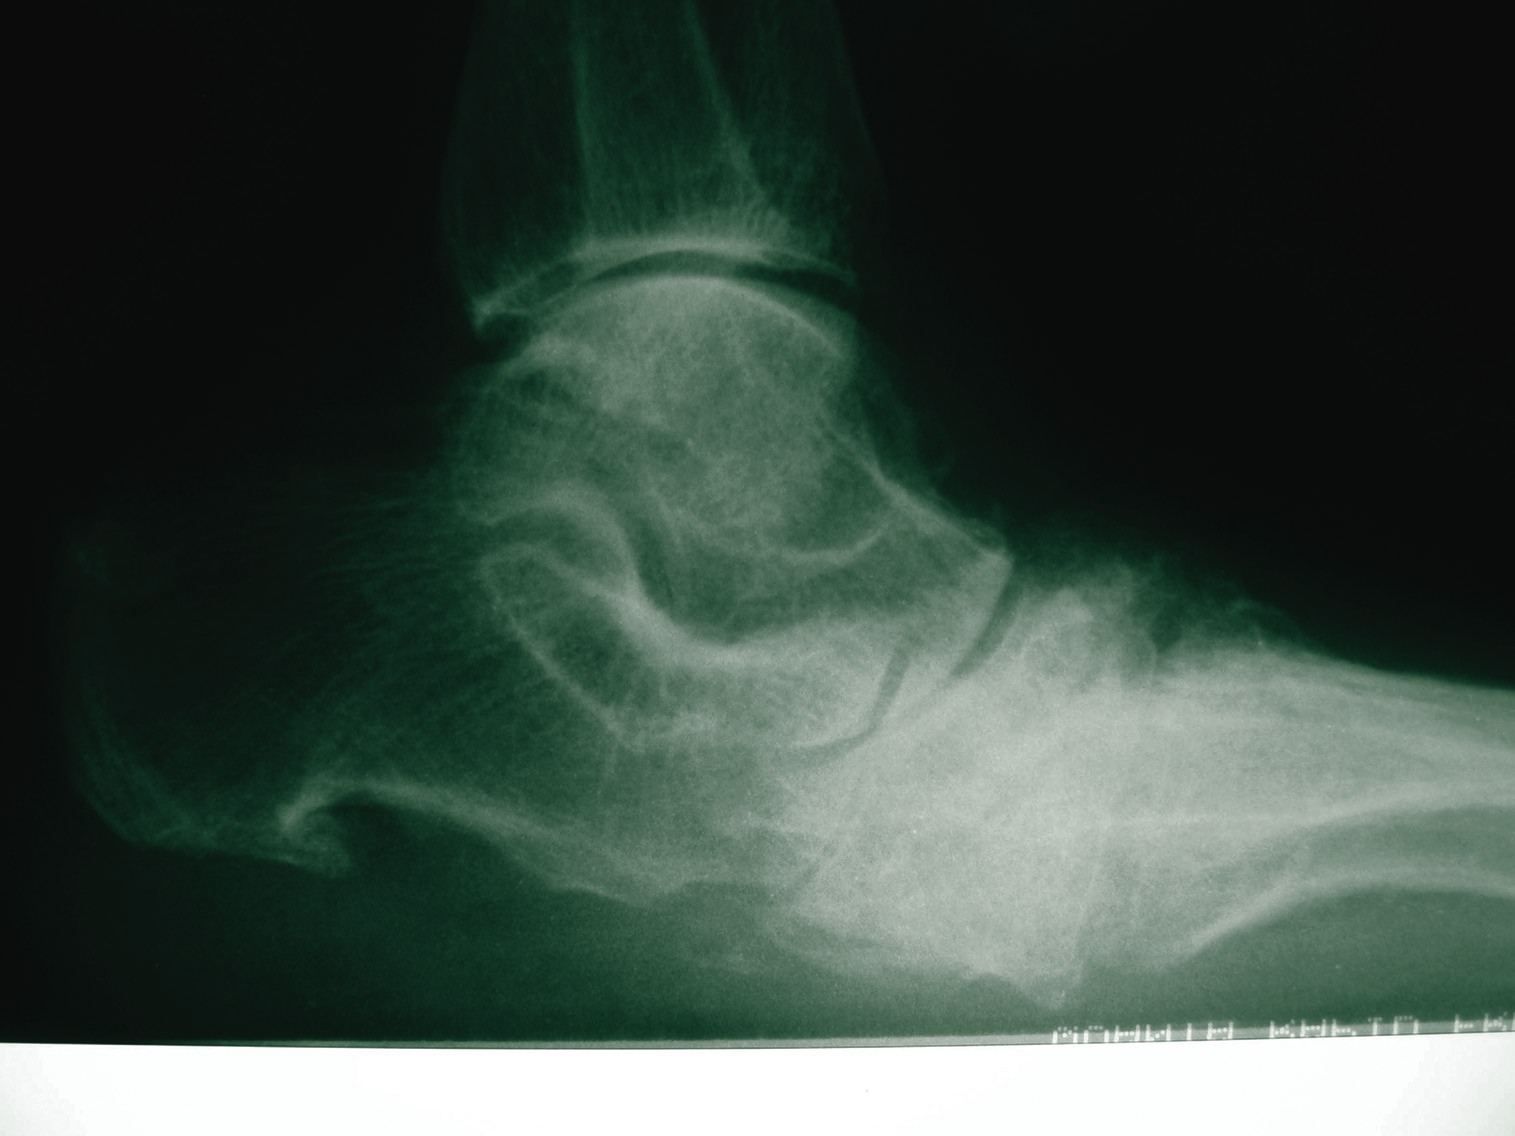

Charcot’s arthropathy is a devastating complication of diabetes mellitus that frequently leads to permanent disability, ulceration and amputation. It is a rapidly progressive and severe form of arthritis. Researchers have equated the acute Charcot foot to a medical emergency since therapies are available that may alter its natural history.1 Unfortunately, the pathophysiology and development are poorly understood. This is frequently complicated by a delay in diagnosis until bony destruction is visible on plain radiographs. This delay often leads to worse outcomes.2 One study found the diagnostic delay averaged 29 weeks.3 Other inflammatory arthridities have treatments that are targeted at the pathophysiologic pathway. For example, there are disease modifying anti-rheumatic drugs (DMARDS) for rheumatoid arthritis (RA). In fact, the standard of care has changed for RA to the point that one should attempt using a DMARD for all patients with RA and not continue endless palliation with only anti-inflammatory medications.4 Perhaps we should approach the treatment of Charcot’s arthropathy, which behaves like an accelerated inflammatory arthritis, in a similar manner to that of RA. Though the exact pathophysiologic mechanisms of this disease process are yet undiscovered, it is generally accepted that trauma (macrotrauma or repetitive moderate trauma) leads to an inflammatory process, which increases blood flow in the extremity. Surprisingly, patients with Charcot have preserved vascular responsiveness in comparison to ulcerated neuropathic patients without Charcot.5 This intact reactivity helps to explain the intense warmth of the affected extremity, which is often 9 to 11ºF higher than the same point on the contralateral limb.6 The hyperemia and inflammation lead to focal osteopenia, allowing joint fragmentation and subluxation. In studies utilizing bone densiometry, researchers have shown the osteopenia.7,8 Researchers showed focalization of the bone loss to the foot in one study which compared the bone mineral density (BMD) of the foot with that of the lumbar spine in those with acute Charcot versus a set of age- and sex-matched controls. The Charcot foot had a T-score three standard deviations below normal (which denotes osteoporosis) in comparison to controls. Yet there was no difference in the stiffness of the lumbar spine between the two groups.7 Other authors have recently discovered the role that the receptor activator of nuclear factor kappa B ligand (RANK-L) plays with osteoporosis and the calcification of vascular smooth muscle cells. They theorize that there is a common thread between the decrease in bone mineral density and the concomitant Mönkeburg’s arteriosclerosis that occurs in patients with Charcot’s arthropathy.9 From what little information that already exists about the disease process, we know that when it comes to treating acute Charcot, we can target our current and future therapies to: • reduce or eliminate trauma; • reduce joint inflammation; and • increase the bone mineral density.